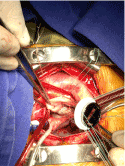

Institutional echocardiogram showed (Figure 1):

Figure 1. Echocardiographic study.

1. Infectious endocarditis Severe mitral.

2. Insufficiency secondary to perforation of the posterior leaflet "storm" with vena contract of 6.6 mm

3. level Greenery pedicle posterior mitral cusp of 11 × 6 mm diameter

4. Auricula dilated left with signs of volume overload

5. Pulmonary Hypertension mild psap 40 mmHg

6. preserved left ventricular function

7. No pericardial effusion in the current study